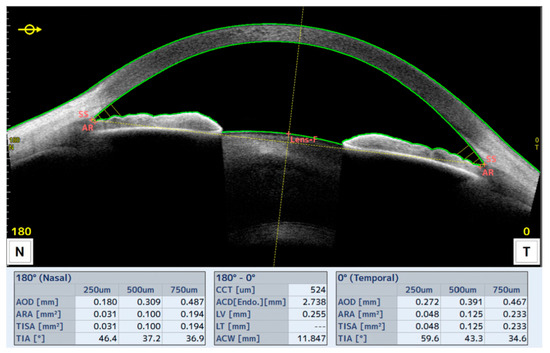

Anterior Segment Variations After Cataract Surgery in Subjects with Primary Open-Angle Glaucoma

Background: The impact of cataract surgery on anterior segment structures in subjects affected by primary open-angle glaucoma (POAG) remains incompletely understood. The aim of this study was to characterize changes in anterior segment parameters after cataract surgery in POAG subjects compared with non-glaucoma [...] Read more.

Background: The impact of cataract surgery on anterior segment structures in subjects affected by primary open-angle glaucoma (POAG) remains incompletely understood. The aim of this study was to characterize changes in anterior segment parameters after cataract surgery in POAG subjects compared with non-glaucoma subjects (control). Methods: A prospective comparative study was conducted, including patients scheduled for cataract surgery who underwent a comprehensive ophthalmic examination before and after surgery using anterior segment optical coherence tomography (OCT). Longitudinal changes and between-group comparisons were analyzed. Results: The results demonstrated a significant enlargement of the anterior chamber and iridocorneal angles after surgery in both groups (p < 0.05), with no significant differences between POAG and control eyes (p > 0.05). Several preoperative parameters, particularly angle-related metrics, were correlated with postoperative anatomical changes, suggesting their potential role as predictors of anterior segment variation (R > 0.50; p < 0.05). Conclusions: In conclusion, this study provides a detailed characterization of anterior segment changes in POAG subjects following cataract surgery, demonstrating anterior chamber enlargement comparable to that observed in non-glaucoma eyes, which may assist clinicians in the management of glaucoma. Full article